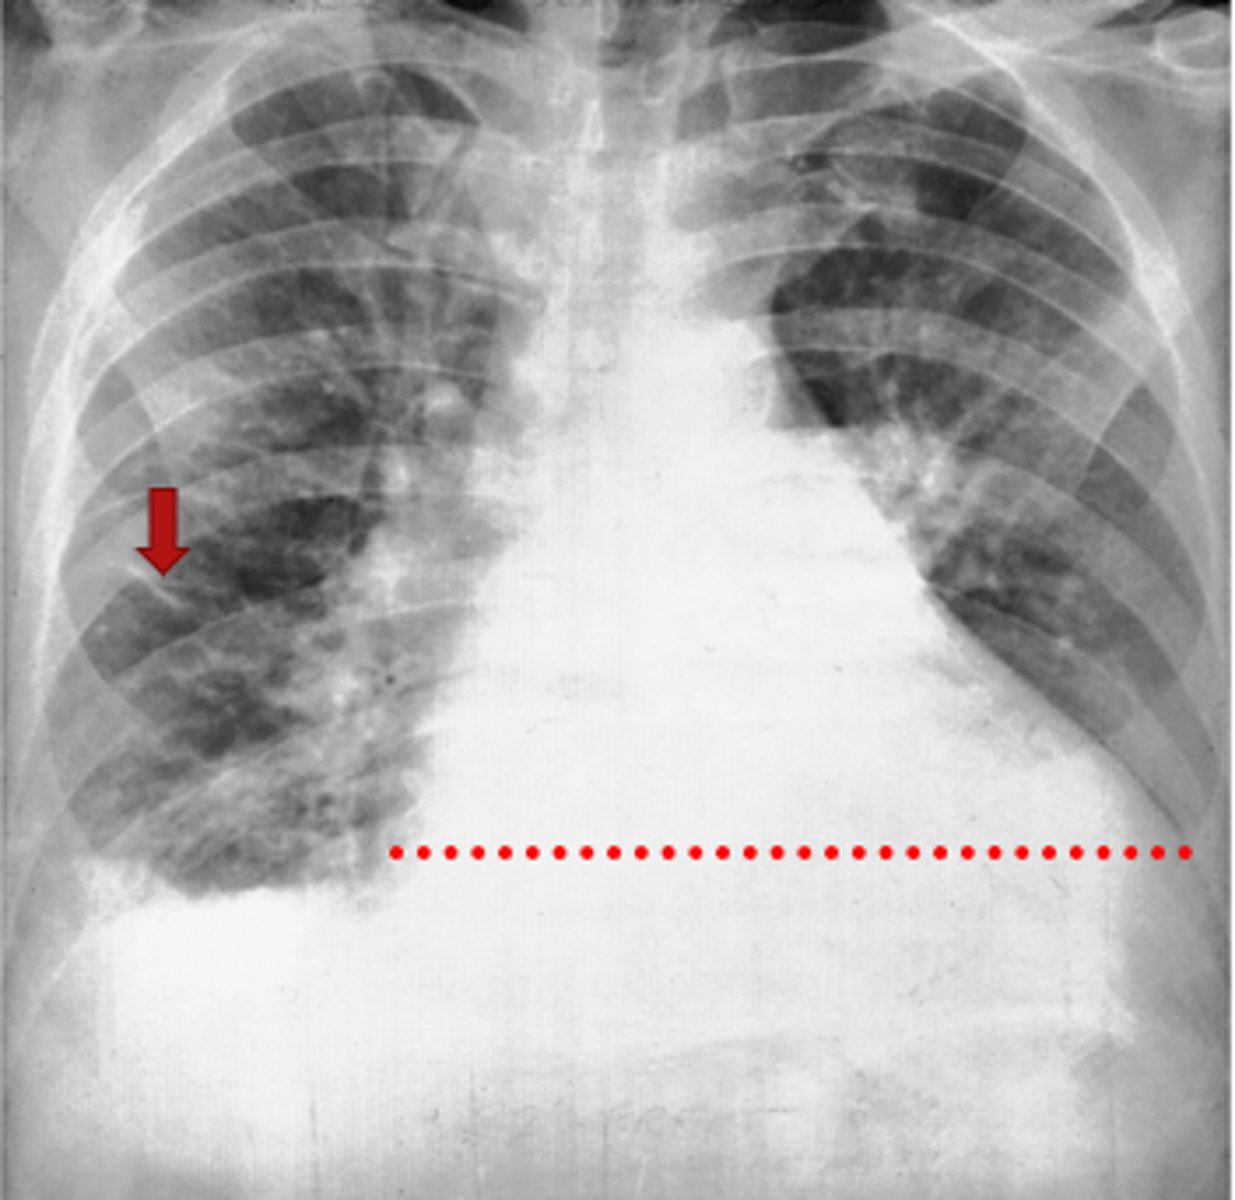

Left lung

Where is the abnormality located in the chest?

Atelectasis

What is the red arrow indicating?

Effusion

What is the likely interpretation?

Pleural Effusion (blunting and whiteouts) (types of effusions include small, large, transudate, and exudate)

Interpretation?